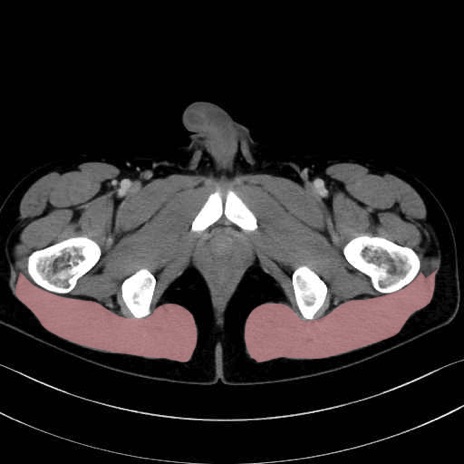

梨状筋 (Piriformis)

内閉鎖筋 (Obturator internus)

外閉鎖筋 (Obturator externus)

大腿方形筋 (Quadratus femoris)